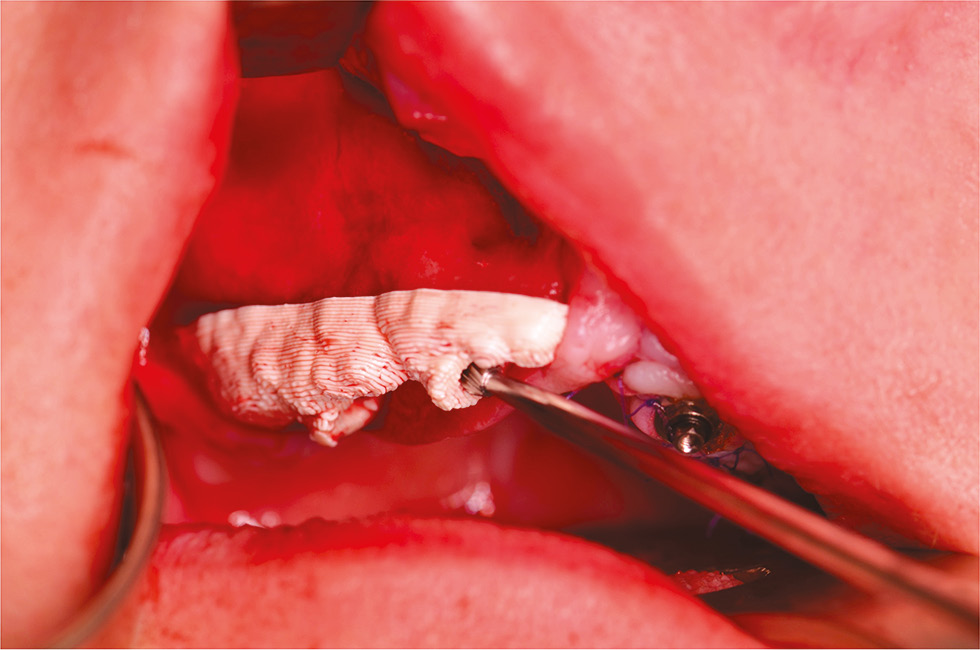

Плотность кости (классификация C. Misch) в скуловой области по данным томографии до лечения и на момент контрольного осмотра (6 лет) превышала 850 HU, что соответствует здоровой кости (D1), состояние костной ткани в области фиксации скуловых имплантатов определено как удовлетворительное (рис. 13, 14).

Рис. 14. Измерение плотности кости в скуловой области: a — до лечения; b — через 6 лет.

Fig. 14. Measurement of bone density in the zygomatic region: a — before treatment; b — after 6 years.